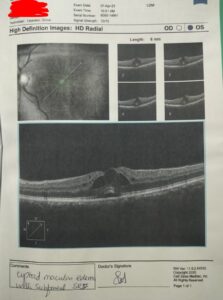

The scan taken on  12th august 2025, four months later, shows a claear reduction in macular edema and subfoveal fluid. The cystoid spaces are less pronounced and the retinal architecture is more preserved, this suggests a positive response.